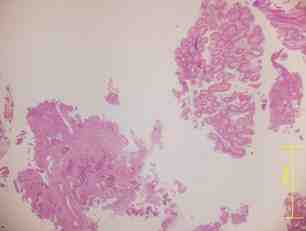

Figura 2. Anatomía Patológica (AP): adenocarcinoma invasivo de colon

Figura 4. AP: regresión 4 de Dworak, ulceración y fibrosis